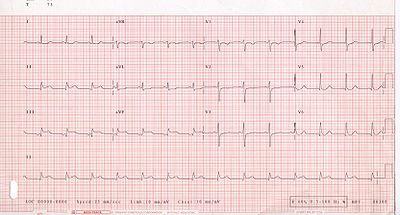

Electrocardiogram

The primary purpose of the electrocardiogram is to detect ischemia or acute coronary injury in broad, symptomatic emergency department populations. However, the standard 12 lead ECG has several limitations. An ECG represents a brief sample in time. Because unstable ischemic syndromes have rapidly changing supply versus demand characteristics, a single ECG may not accurately represent the entire picture. It is therefore desirable to obtain serial 12 lead ECGs, particularly if the first ECG is obtained during a pain-free episode. Alternatively, many emergency departments and chest pain centers use computers capable of continuous ST segment monitoring. The standard 12 lead ECG also does not directly examine the right ventricle, and is relatively poor at examining the posterior basal and lateral walls of the left ventricle. In particular, acute myocardial infarction in the distribution of the circumflex artery is likely to produce a nondiagnostic ECG. The use of additional ECG leads like right-sided leads V3R and V4R and posterior leads V7, V8, and V9 may improve sensitivity for right ventricular and posterior myocardial infarction. In spite of these limitations, the 12 lead ECG stands at the centre of risk stratification for the patient with suspected acute myocardial infarction. Mistakes in interpretation are relatively common, and the failure to identify high risk features has a negative effect on the quality of patient care.

The 12 lead ECG is used to classify patients into one of three groups:

- those with ST segment elevation or new bundle branch block (suspicious for acute injury and a possible candidate for acute reperfusion therapy with thrombolytics or primary PCI),

- those with ST segment depression or T wave inversion (suspicious for ischemia), and

- those with a so-called non-diagnostic or normal ECG.

A normal ECG does not rule out acute myocardial infarction. Sometimes the earliest presentation of acute myocardial infarction is the hyperacute T wave, which is treated the same as ST segment elevation. In practice this is rarely seen, because it only exists for 2-30 minutes after the onset of infarction. Hyperacute T waves need to be distinguished from the peaked T waves associated with hyperkalemia. The current guidelines for the ECG diagnosis of acute myocardial infarction require at least 1 mm (0.1 mV) of ST segment elevation in the limb leads, and at least 2 mm elevation in the precordial leads. These elevations must be present in anatomically contiguous leads. (I, aVL, V5, V6 correspond to the lateral wall; V1-V4 correspond to the anterior wall; II, III, aVF correspond to the inferior wall.) This criterion is problematic, however, as acute myocardial infarction is not the most common cause of ST segment elevation in chest pain patients. Over 90% of healthy men have at least 1 mm (0.1 mV) of ST segment elevation in at least one precordial lead. The clinician must therefore be well versed in recognizing the so-called ECG mimics of acute myocardial infarction, which include left ventricular hypertrophy, left bundle branch block, paced rhythm, early repolarization, pericarditis, hyperkalemia, and ventricular aneurysm.

Left bundle branch block and pacing interferes with the electrocardiographic diagnosis of acute myocadial infarction by making the ST segment uninterpretable. The GUSTO investigators Sgarbossa et al. developed a set of criteria for identifying acute myocardial infarction in the presence of left bundle branch block and paced rhythm. They include concordant ST segment elevation > 1 mm (0.1 mV), discordant ST segment elevation > 5 mm (0.5 mV), and concordant ST segment depression in the left precordial leads. The presence of reciprocal changes on the 12 lead ECG may help distinguish true acute myocardial infarction from the mimics of acute myocardial infarction. The contour of the ST segment may also be helpful, with a straight or upwardly convex (non-concave) ST segment favoring the diagnosis of acute myocardial infarction.

The constellation of leads with ST segment elevation enables the clinician to identify what area of the heart is injured, which in turn helps predict the so-called culprit artery.

As the myocardial infarction evolves, there may be loss of R wave height and development of pathological Q waves (defined as Q waves deeper than 1 mm and wider than 1 mm.) T wave inversion may persist for months or even permanently following acute myocardial infarction. Typically, however, the T wave recovers, leaving a pathological Q wave as the only remaining evidence that an acute myocardial infarction has occurred.